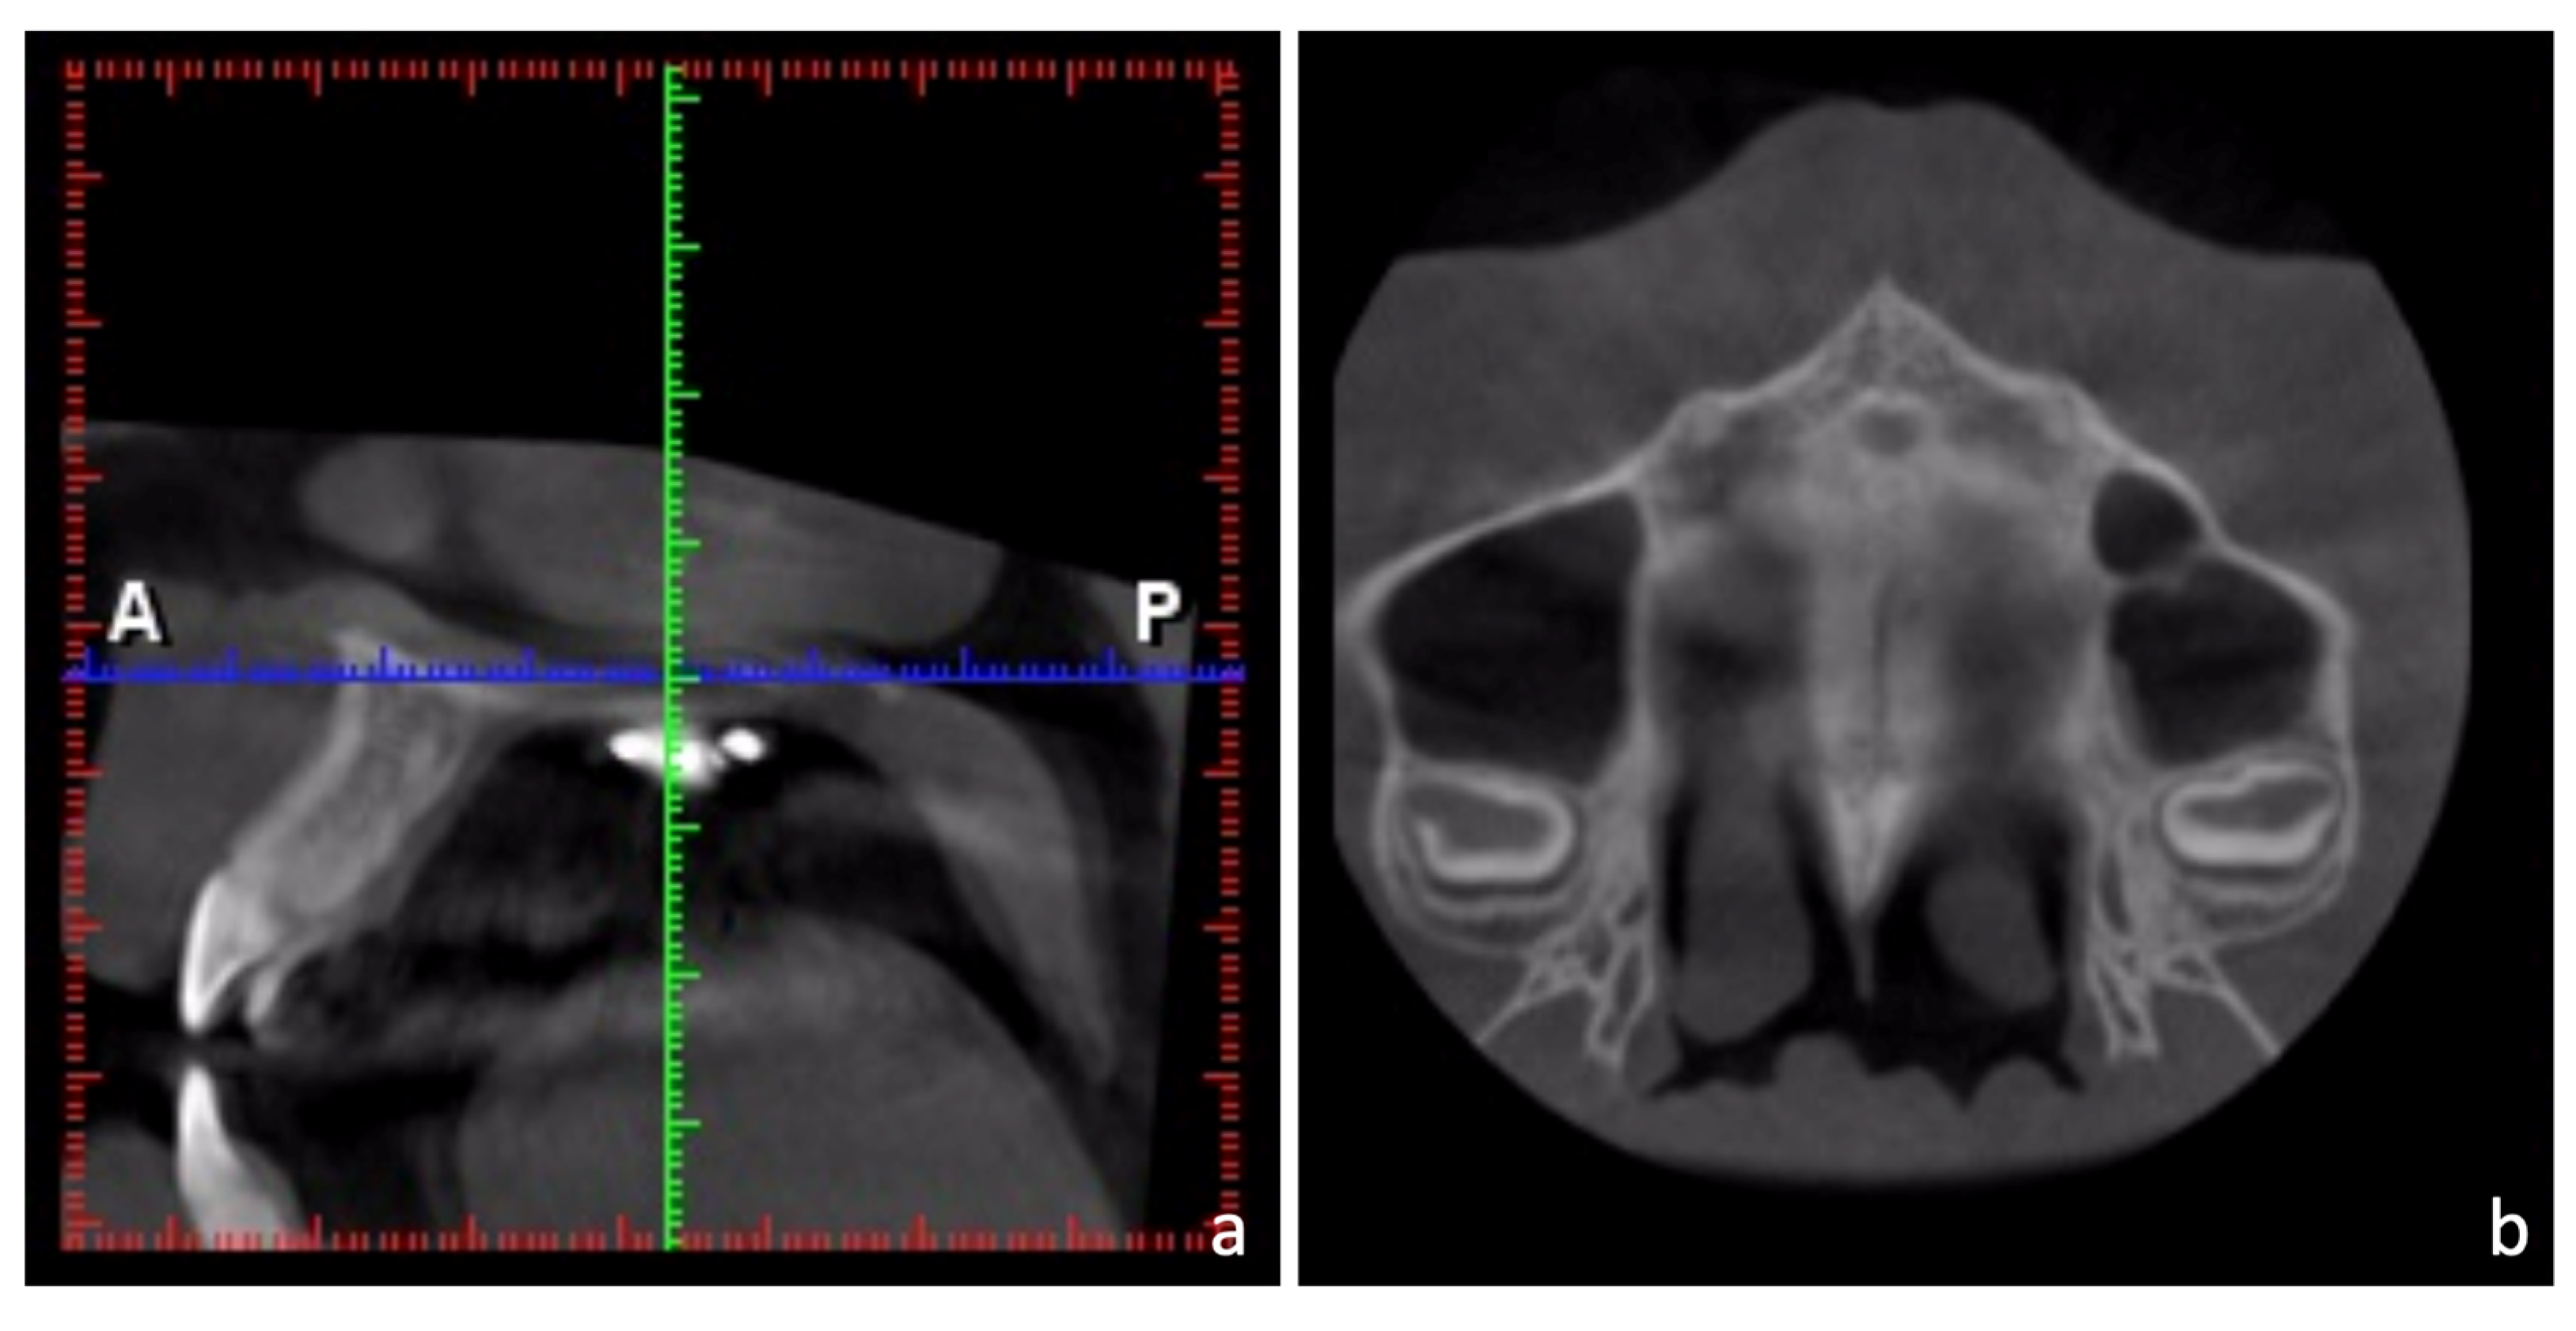

2.3. Treatment Progress

2.4. Treatment Results